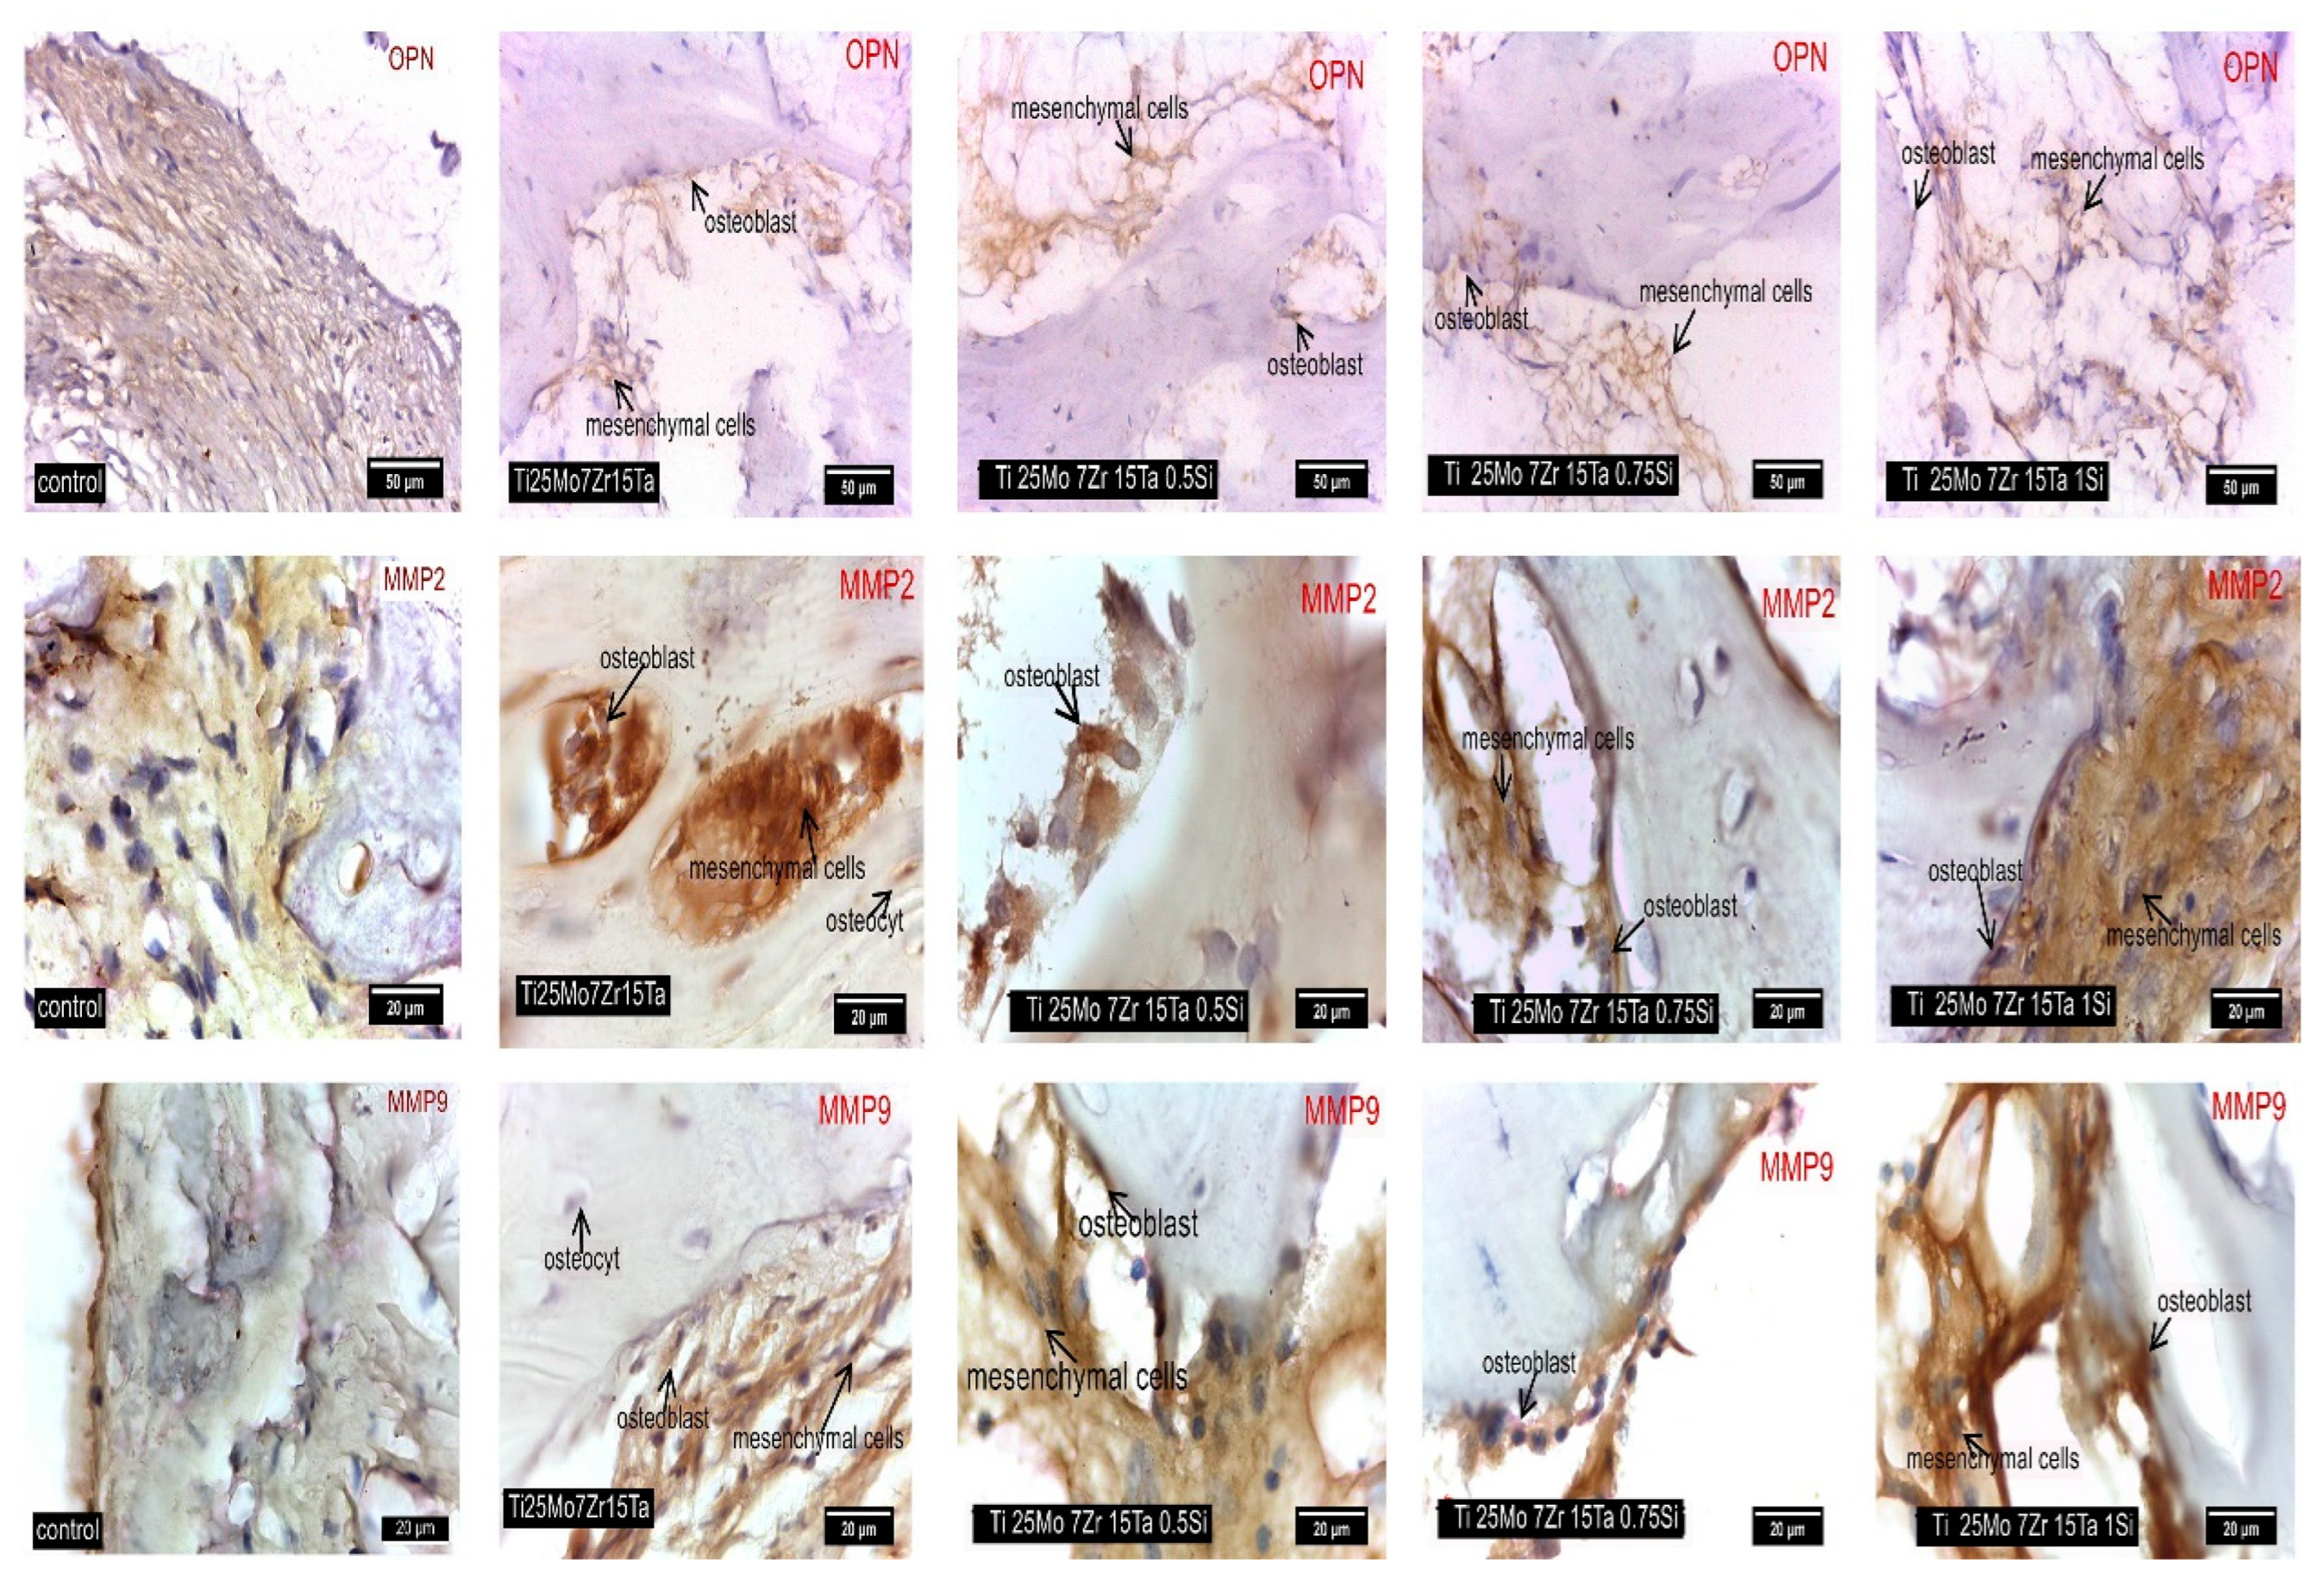

3.3. Interpretation of Results, Radiographs and Micrographs